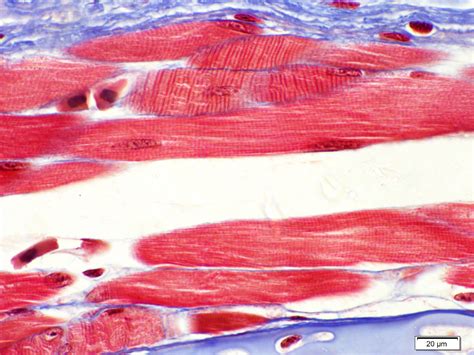

Un muscle strié squelettique est un type de muscle qui est présent dans notre corps et qui est responsable du mouvement des os. Ces muscles sont également appelés muscles volontaires, car ils sont contrôlés par notre volonté et notre cerveau. Ils sont caractérisés par leur structure striée, qui est visible à l’œil nu grâce à leurs bandes transversales appelées « stries ».

Les muscles striés squelettiques fonctionnent grâce à l’action des fibres musculaires, qui sont des cellules spécialisées capables de se contracter. Lorsque notre cerveau envoie un signal aux fibres musculaires, elles se contractent et causent un mouvement dans l’os associé au muscle. Par exemple, lorsque nous levons notre bras, c’est grâce aux muscles striés squelettiques de notre bras qui se contractent et qui permettent ce mouvement.